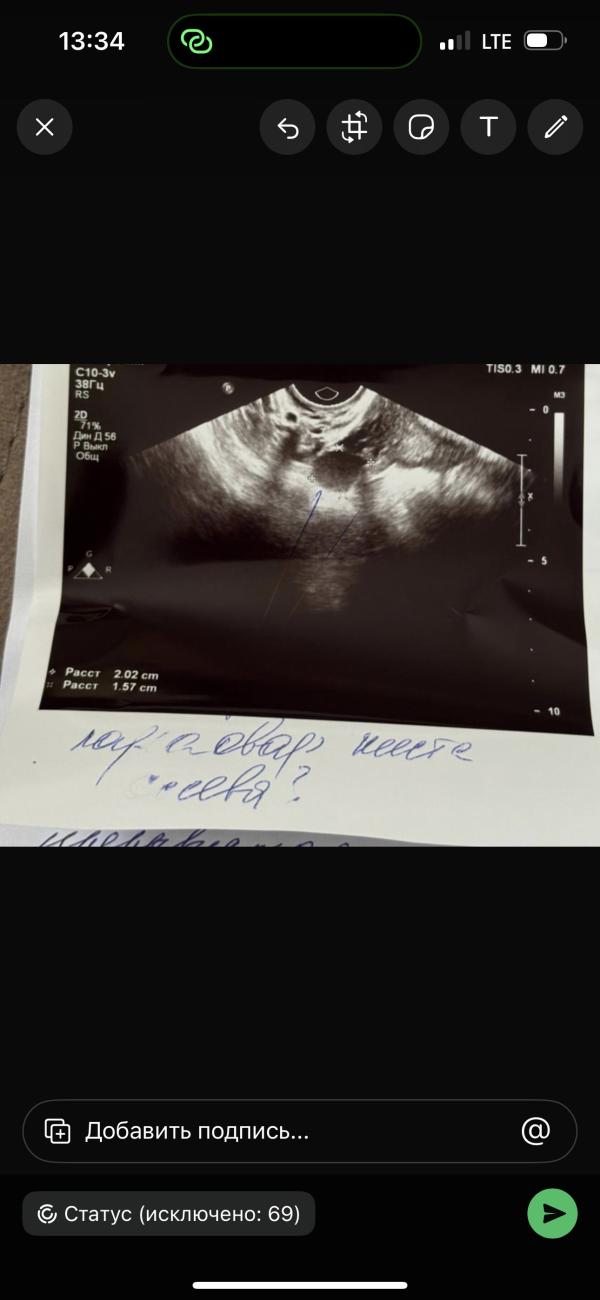

Девочки что тут написано, я не поняла 🥲

Параовариальная киста слева

@fatis, у меня была и сама ушла. Ее только в динамике наблюдают , не оперируют . Сама может рассосаться , главное чтоб не увеличилась .